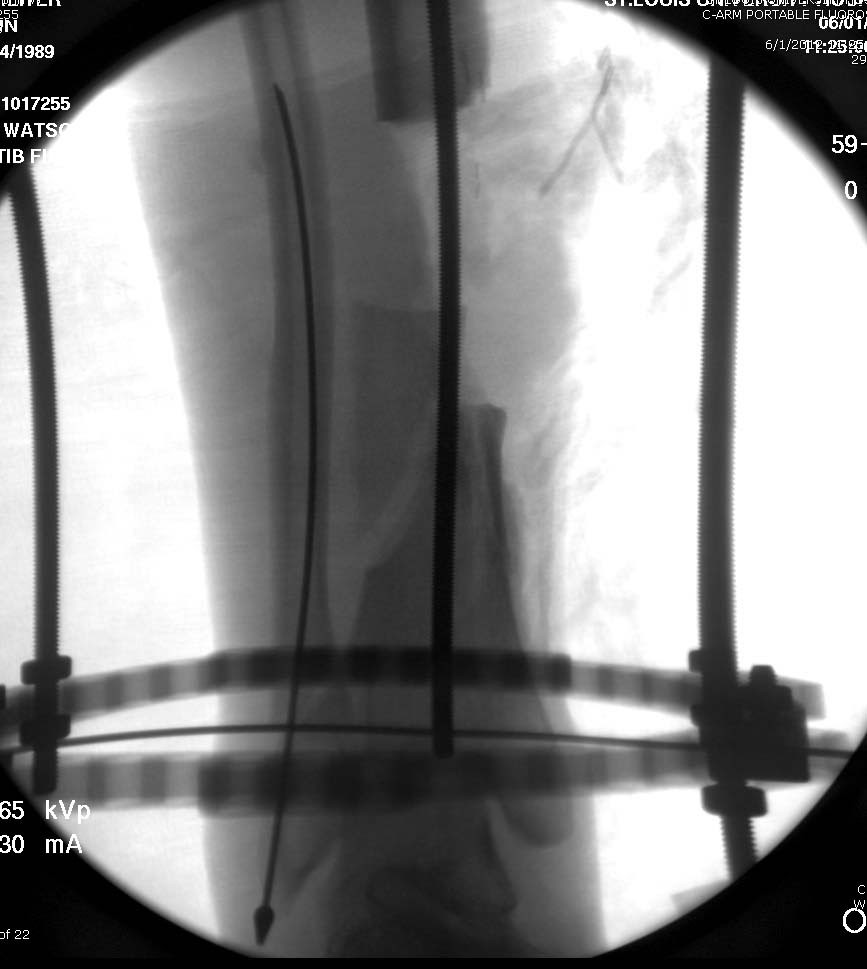

Данный случай не огнестрельная рана, а результат мотоциклетной аварии. Независимо от повреждения при таких обширных дефектах мягких и костной тканей применяется схожая тактика. Как видно, после нескольких I&D для создания “pseudo membrane” применили цилиндрический блок из цемента. Дефект мягких тканей закрыли свободным Anterior Thigh Graft. Из малого доступа цилиндр удален небольшими кусочками, а пространство заполнили бусами для освобождения пространства. По мере приближения регенерата освободили пространство удалением бус через небольшой разрез. Этап созревание регенерата можно было ускорить усилением интрамедуллярным гвоздем, но решили закончить методом Илизарова.

Теперь по поводу данного случая - “спейсер” из цемента предупреждает инфекцию и сохраняет пространство. Но вместо “бус” “цилиндрическая форма” более удобная, вокруг нее образуется ровная трубчатая поверхность “псевдо-мембраны” что в дальнейшей позволит закрыть небольшие дефекты “графтом” или во время удлинения облегчает скольжение регенерата как по трубке.